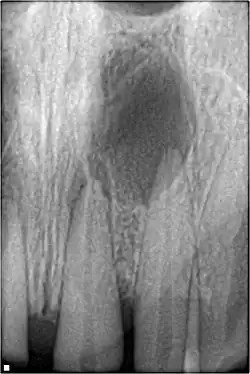

Pulpal necrosis

Pulp necrosis usually occurs either as ischaemic necrosis (infarction) caused by disruption to the blood supply at the apical foramen or as an infection-related liquefactive necrosis following dental trauma (2). Signs of pulpal necrosis include[42]

- Persistent grey colour to tooth that does not fade

- Radiographic signs of periapical inflammation

- Clinical signs of infection: tenderness, sinus, suppuration, swelling

Treatment options will be extraction for the primary tooth. For the permanent tooth, endodontic treatment can be considered.

Pulpal obliteration

4–24% of traumatized teeth will have some degrees of pulpal obliteration that is characterized by the loss of pulpal space radiographically and yellow discolouration of the clinical crown. No treatment is needed if it is asymptomatic. Treatment options will be extraction for symptomatic primary tooth. For symptomatic permanent tooth, root canal treatment is often challenging because the pulp chamber is filled with calcified material and the drop-off sensation of entering a pulp chamber will not occur.[44]